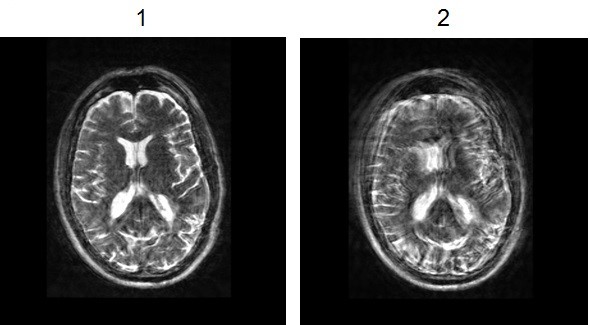

| Number | Description |

|---|---|

| 1 | Cube T2 axial reformatted image with PROMO turned On. |

| 2 | Cube T2 axial reformatted image with PROMO turned Off. |

Use PROMO to prospectively correct for patient motion when acquiring 3D images.